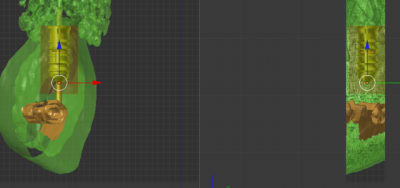

Dans un post précédent j'avais dit trouvé la 22 trop "angulée"

une petite coupe maintenant que j'y arrive

en bleu l'os alvéolaire

en vert le guide

en orange le fx moignon léone angulé 15°

coupe2mm